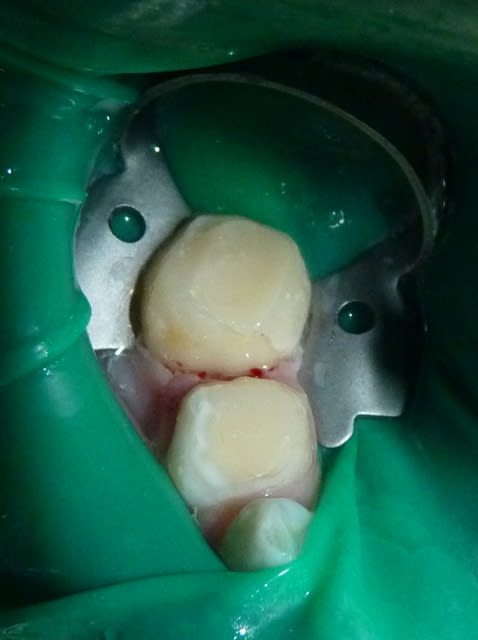

05/07/11 : secteur IV.

85 n'a plus de parois vestibulaire/linguale. 84 n'a plus de paroi linguale.

J'utilise un composite plutôt qu'un CVI pour une meilleure adhésion et résistance mécanique sur ces dents très délabrées. J'essaie de recréer des bombés sur les moignons.